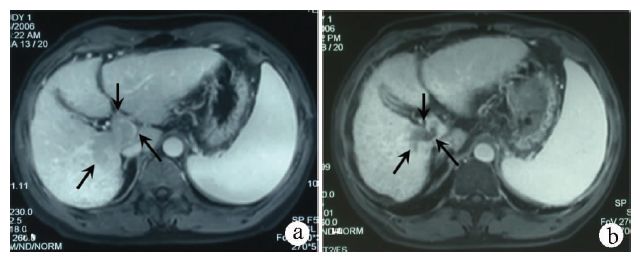

上海东方肝胆外科医院进行一项随机前瞻多中心的临床研究[4],比较肝细胞癌伴门静脉癌栓患者的术前新辅助放疗与不放疗的生存情况,放疗组82例,给予18 Gy/6次的新辅助外放疗;对照组82例,未行新辅助放疗。结果显示:新辅助放疗组的1、2年生存率分别为75.2%、27.4%,对照组分别为43.1%,9.4%,两组生存率有统计学差异(P<0.001)。新辅助放疗明显提高肝细胞癌患者的术后生存期。病例2是门静脉主干癌栓,经过新辅助放疗,癌栓从程氏Ⅲ型降为Ⅱ型,最后获得手术切除(图2)。

注:a,放疗前MRI检查,发现门静脉主干和右后支癌栓(箭头所示);b,放疗后3个月随访MRI,癌栓明显缩小,血供减少(箭头所示),患者获得切除机会。

图2 新辅助放疗后门静脉癌栓程氏Ⅲ型降为程氏Ⅱ型